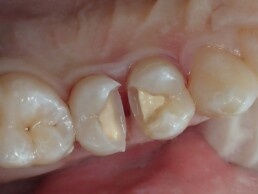

La bio greffe représente un traitement alternatif à des soins plus mutilants(couronne prothétique)quand bien sûr cela est possible !

Globalement, on considère ce traitement comme additif(d’où la greffe)et ce à l inverse d’un traitement soustractif(comme c’est le cas pour une prothèse ou on enlève l émail pour donner la place à la future couronne)

Remarquons que dans le cas du traitement dit soustractif on enlève plus de tissu sain que nécessaire pour reconstruire !